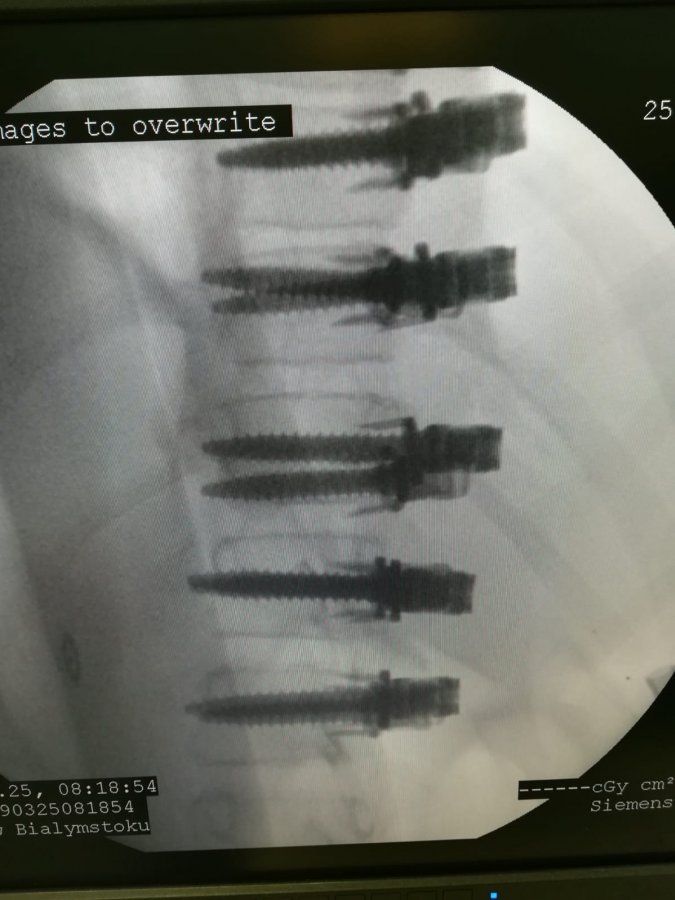

- Zaprosiliśmy do siebie doktora Darryla Antonacci z Nowego Jorku z Uniwersytetu Princeton. Jest on jednym z twórców metody ASC (ang. Anterior Scoliosis Correction), która moim zdaniem, jest rewolucją w leczeniu skolioz. Do tej pory leczenie polegało na odprostowaniu kręgosłupa i zaimplantowaniu sztywnych prętów. One ten kręgosłup usztywniały do końca życia. Owszem, w stosunku do tego co było przed operacją, komfort życia się poprawiał. Jednak aktywność fizyczna takiego pacjenta nie jest tą, o jakiej marzymy jako lekarze. Nie ma mowy o tańcu, balecie, czy zawodowym uprawianiu sportu. Dlatego też ortopedzi stosowali takie zabiegi tylko w dużych deformacjach. Punktem wyjścia dla techniki ASC była metoda VBT (ang. Vertebral Body Tethering), która może być zastosowana tylko dla pacjentów nadal rosnących. Natomiast technika ASC autorstwa dr Antonacci, dr Betz i dr Cuddihy polega na tym, że można ją zastosować nawet u pacjenta z zakończonym wzrostem kostnym. Technika ASC polega na wstępnym uelastycznieniu deformacji, implantacji specjalnych śrub do trzonów kręgów i ostatecznie korekcji skrzywienia poprzez połączenie implantów elastyczną taśmą. Technikę tę można stosować zarówno u pacjentów w trakcie wzrostu, jak również po jego zakończeniu. W przypadku pacjenta nadal rosnącego wstępna korekcja jest częściowa, kolejna dokonuje się w trakcie wzrastania poprzez blokowanie chrząstek wzrostowych trzonów po stronie wypukłej skrzywienia. Trudnością jest właściwe zaplanowanie, jak również sama technika zabiegu, która jest bardzo wymagająca. Taki zabieg doktor Antonacci wykonał dla jednej z tancerek, finalistek w angielskiej wersji „Mam Talent”. Na zabieg do Nowego Jorku wysłał ją jeden z jurorów. A dziewczyna nadal tańczy w swoje grupie i spełnia swoje marzenia.

- Nie. To mogą być krzywizny rzędu 70, a nawet 90 stopni. Oczywiście pacjent musi przejść kwalifikację do zabiegu. Co ciekawe, metodę VBT i ASC w ortopedii wykorzystujemy od bardzo dawna. Korygujemy nią zaburzenia osi kończyn górnych i dolnych u dzieci blokując czasowo chrząstki wzrostowe. Nigdy jednak tego nie robiliśmy w kręgosłupie. Ten zabieg wykonamy jako pierwsi w kraju. W Europie tylko cztery ośrodki tak operują. W USA też tych zabiegów nie jest dużo.

Moim marzeniem jest ortopedia małoinwazyjna, artroskopowa. Jestem skłonny do zastąpienia naszych tradycyjnych narzędzi małymi dostępami i manipulatorami z kamerą. Właśnie dr Antonacci jest osobą, która preferuje małoinwazyjne zabiegi operacyjne. Są już opracowane techniki korekcji skrzywienia kręgosłupa za pomocą torakoskopu. Wtedy już nie trzeba otwierać klatki piersiowej, żeby zakładać te implanty, a można je wkładać do kręgosłupa jak przez dziurkę do klucza.